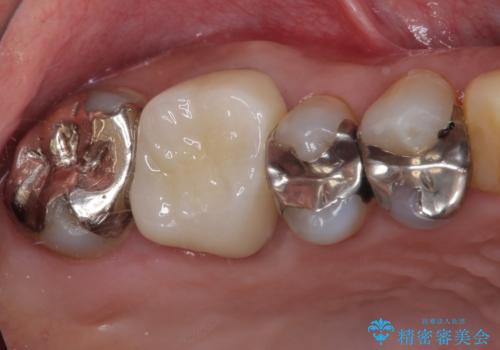

- 仮歯装着後に放置してしまい、恥ずかしいとのことで来院された患者様です。

仮歯が不適合で歯肉が腫脹していたため、しっかりと調整した新しい仮歯にして腫れを改善した上で、オールセラミッククラウンにて補綴することとしました。

日頃の歯磨きをしっかりと行ってくださるので、新しい仮歯に変えてから速やかに歯肉の状態が改善されました。

歯肉からの出血がほとんどないため精度の良い型取りができ、非常に適合の良い補綴治療を行うことができました。